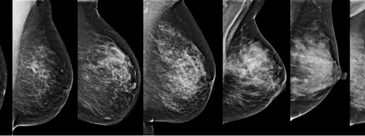

You are not Dense but are your Breasts?

READ ONE – SHARE TWO Read one share TWO this weekend. PLEASE tag TWO women friends, relatives or colleagues and ask them to like and share on FB 👭👭 Smart women know about Being Dense spread the word #breastdensity (.) (.) Breast Density does not discriminate 👭 40% of women have dense breast tissue, many do … More Being dense is not ok – smart women know

American and Japanese breast radiologists are on record to say they cannot see clearly through mammographic Breast Density. Women with dense breasts, in these countries, are informed accordingly and are advised to avail of supplementary breast screening like Ultrasound or MRI. How do American and Japanese women differ from Irish women? Irish women are NOT … More Japanese women now in the know about being dense